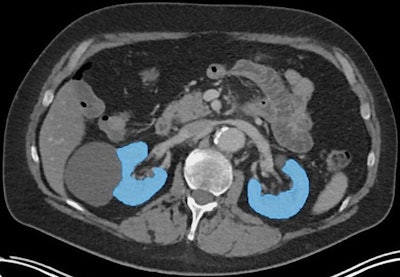

An axial CT image illustrating segmentation of functioning kidney tissue (blue areas), excluding kidney cysts and renal pelvis, using TotalSegmentator. Image and caption courtesy of RSNA.